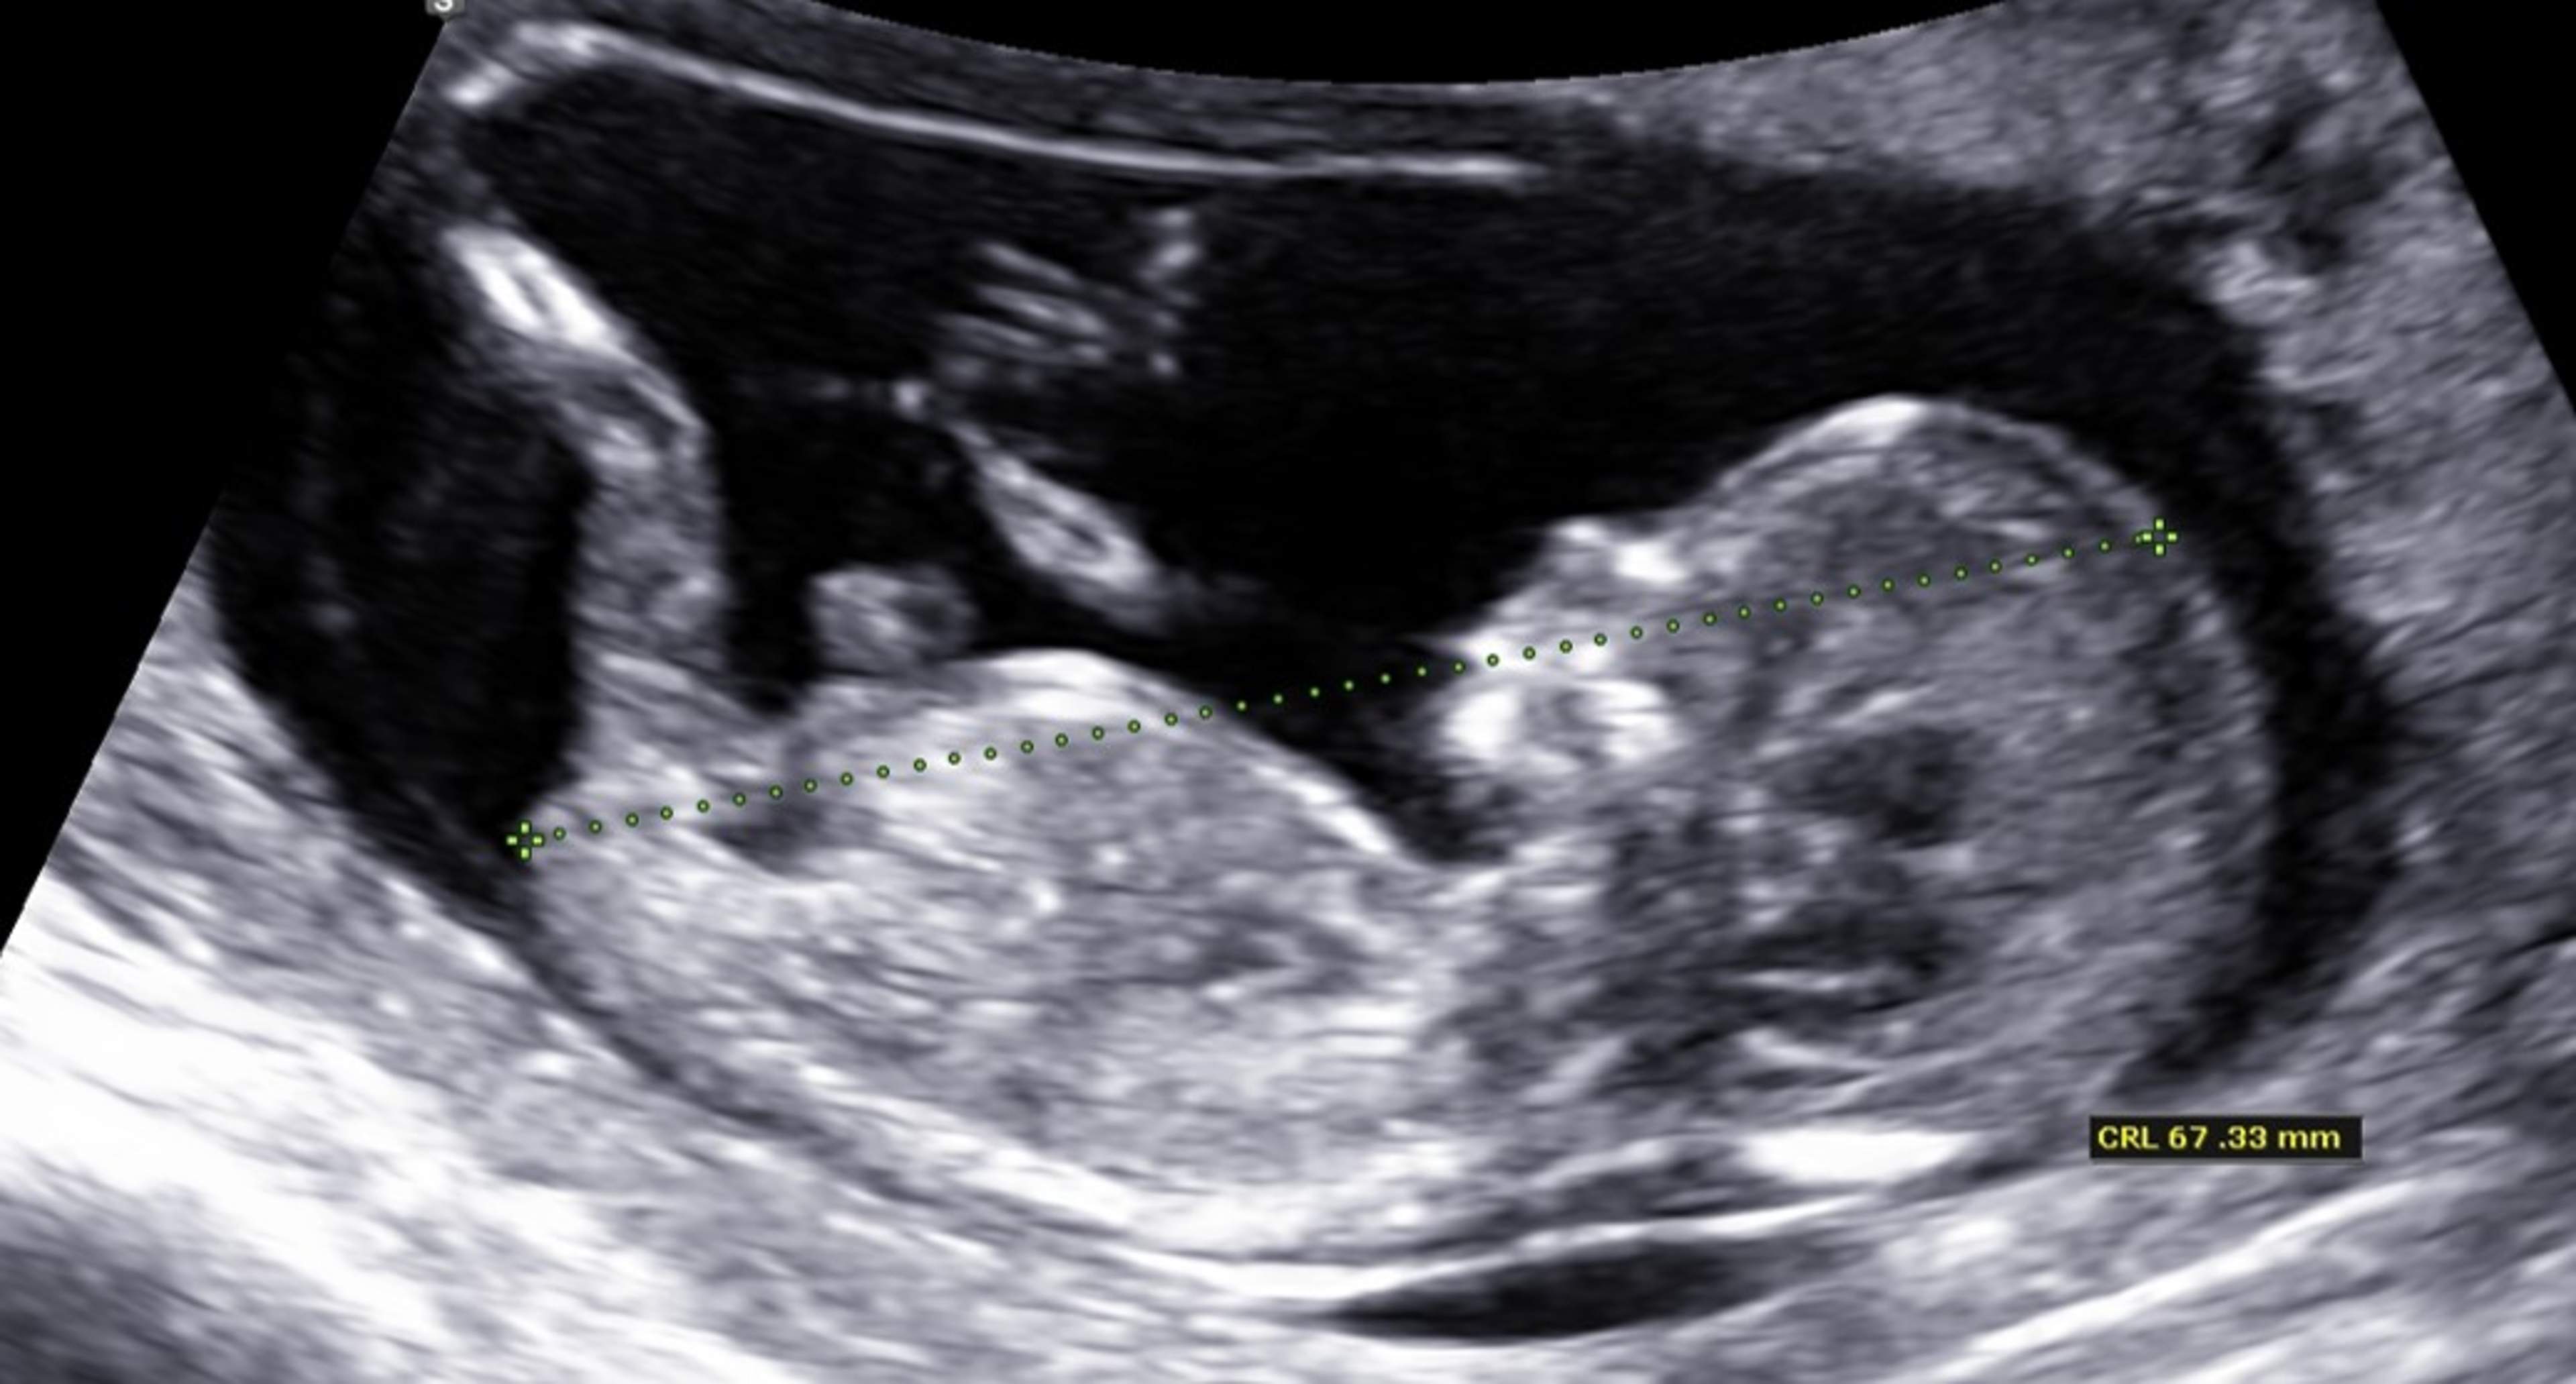

Den slutliga beräknade förlossningstiden fastställs vid den första ultraljudsundersökningen enligt fostrets sitthöjd.

Kombinerad screening omfattar ultraljudsundersökning och blodprov av mamman. Blodprovet analyseras för halter av hormoner och proteiner från moderkakan och fostret. I ultraljudsundersökningen mäts fostrets nackspalt och sitthöjd. Riskbedömningen påverkas också av mammans ålder. Blodprov tas av mamman före ultraljudsundersökningen i graviditetsveckorna 9+0–12+6 och ultraljudsundersökningen görs i graviditetsveckorna 11+0–13+6. Den bästa tidpunkten att besöka laboratoriet är då 10 graviditetsveckor har fullbordats.